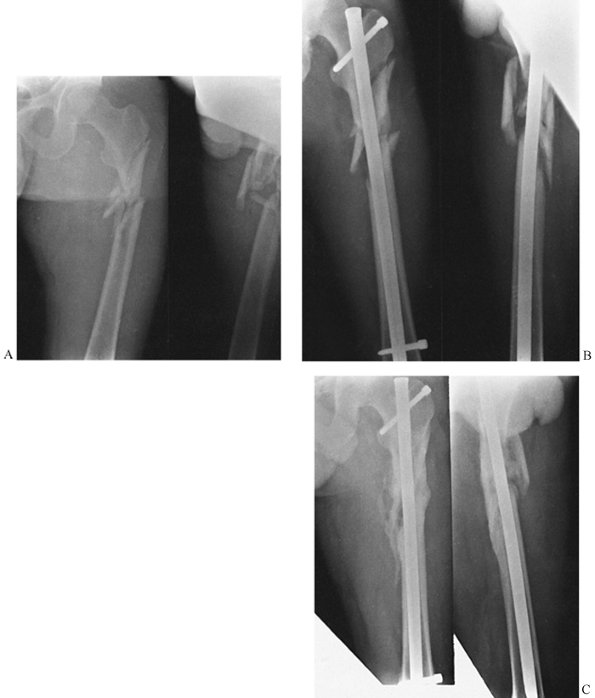

critical. The most recent development has been the antegrade

intramedullary devices such as the Gamma nail, which are very popular

in central Europe but seem to have outcomes similar to sliding hip

screws (8,58,83,144). These are discussed in more detail later in section D on second-generation interlocking nails.